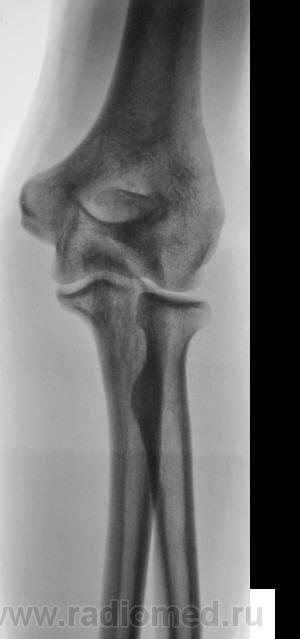

Травма.     Пациент направлен на рентгенографию локтевого сустава.

Перелом локтевого отростка - на операцию

Если рассуждать с точки зрения только диагностики перелома - нет, так как перелом хорошо виден и на стандартных проекциях. С точки зрения дальнейшей лечебной тактики - да. Так как косые проекции выявили безусловную необходимость оперативного лечения.